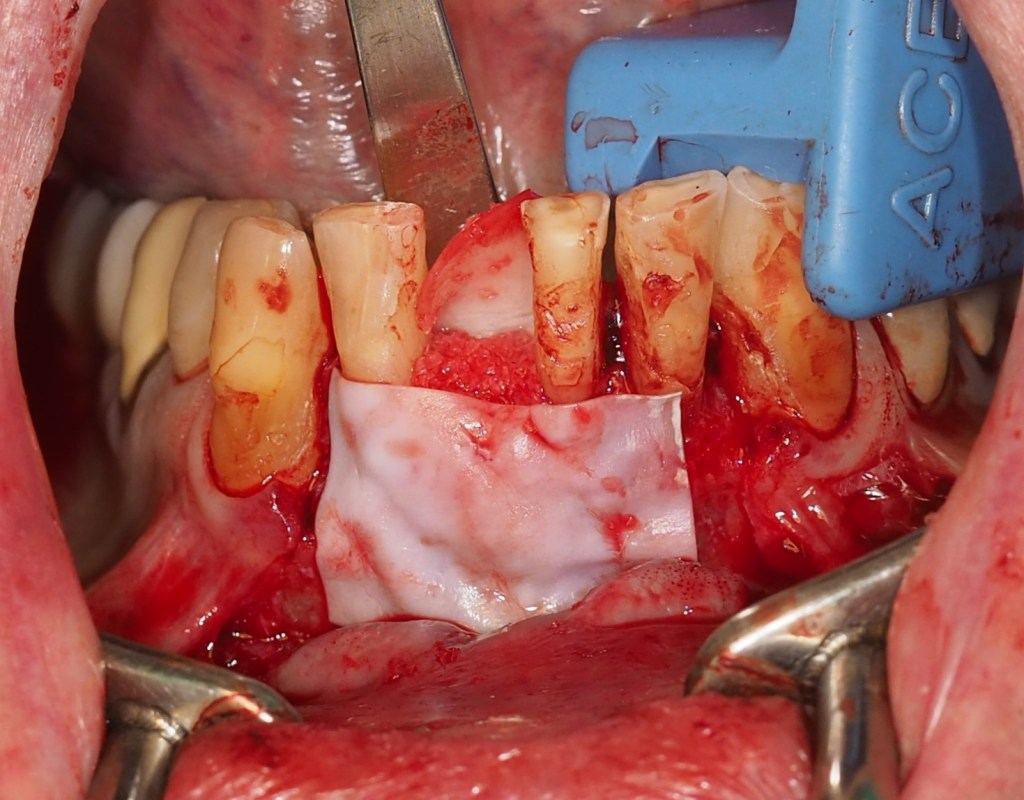

Se decide la extracción del diente 4.1 y la realización de una regeneración ósea guiada mediante el uso de hueso autólogo y membranas reabsorbibles en silla de montar. El diente 3.1 se mantiene de forma estratégica como soporte para una restauración provisional, anticipando su futura extracción en la fase final del tratamiento. En las fotos intraorales de la cirugía, tras la extracción el incisivo y legrado del granuloma, podemos apreciar la ausencia de hueso por vestibular y una perforación en la cortical lingual. (Figuras 9-12).